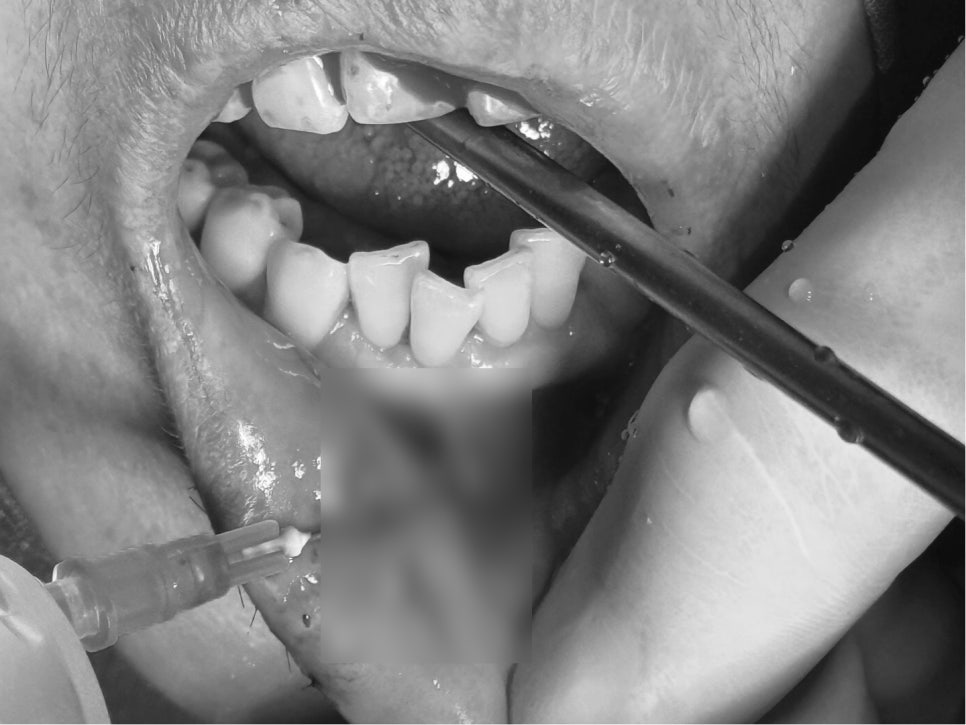

Suturing of multiple lacerations (gums, lips, under the chin)

Because the inside of the mouth contains many bacteria and has a high risk of inflammation,

the torn areas need to be sutured precisely.

The patient had

a laceration inside the gums,

a deep laceration extending into the outer muscle layer of the lip,

and a laceration under the lower jaw,

so suturing was performed separately on the outside and inside.

(oral suturing + facial suturing)

This is an important step to prevent future scarring, changes in lip shape,

and asymmetry in gum height.